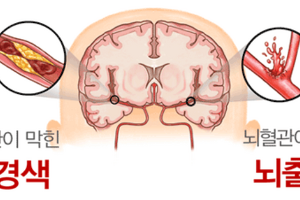

뇌혈관이 막히거나 터지는 질환을 부르는게 뇌졸중이고 그 중 뇌혈관이 막히는게 뇌경색 그리고 뇌혈관이 터지는 것을 뇌출혈이라고 합니다. 뇌졸중은 영구적인 손상이 많다고 하며 증상에 따라 전신이나 육체 일부 기능이 마비되는 등의 극심한 후유증이 남는 무서운 질병입니다 오늘은 뇌경색 초기증상에 대하여 알려드리도록 하겠습니다.